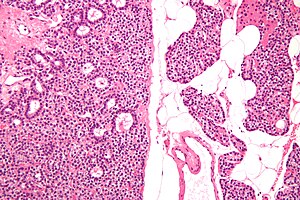

Chief cell parathyroid adenoma (left of image) and unremarkable parathyroid gland (right of image). H&E stain. (WC) | |

| LM | proliferation of parathyroid cells (chief cells, oxyphils or both) usually lacking adipose tissue, +/-rimmed by normal parathyroid gland, lack of destructive invasion of surround structures, lack of metastatic disease |

- Proliferation of parathyroid cells (chief cells, oxyphils or both) usually intermixed lacking adipose tissue.

- +/-Rim of normal parathyroid gland around the lesion[7] with adipose tissue.

Chief cell parathyroid adenoma

Features:[2]

- Chief cells - key feature:

- Small central nucleus.

- Round with stippled chromatin - important.

- Moderate cytoplasm.

- +/-Scattered oxyphil cells:

- Large cells.

- Abundant cytoplasm.

- Architecture:

- Nests.

- Circular formations - often around capillaries (perivascular pseudorosettes).